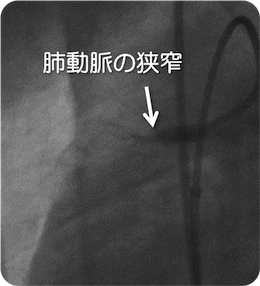

治療前

治療後

慢性肺血栓塞栓性肺高血圧症に対するカテーテル治療

肺動脈のつまりを改善させ、肺動脈圧を低下させることを目的に治療を行います。 バルーンを用いて血管を拡張します。 ほとんどの場合、狭窄ないし閉塞血管は複数あり、数回にわけて治療を行う必要があります。